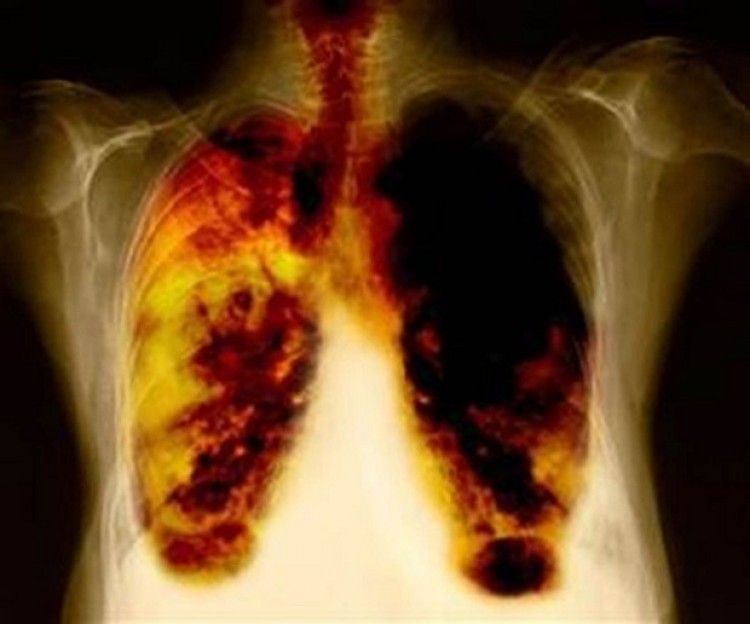

De todos los cánceres, el cáncer de pulmón es la principal causa de muerte por esta enfermedad en el mundo, siendo que una de cada cinco personas que muere de cáncer lo padeció. Asimismo, las estadísticas indican que alrededor del 58% de los casos ocurren en países en vías de desarrollo.¿Qué sucede en nuestro país?En Argentina, el cáncer de pulmón ocupa el primer lugar como causa de muerte por cáncer entre los hombres, y el tercero entre las mujeres por debajo del cáncer de mama y colon.¿A quiénes afecta?Característicamente, afecta más a los hombres y a los grandes fumadores; pero hemos asistido en los últimos años a un cambio progresivo en las características de la población de pacientes. Aunque los hombres fumadores siguen siendo mayoría, hay una proporción creciente de mujeres que lo padecen y, muchas de ellas, no han fumado y son más jóvenes.La principal causa continúa siendo el tabaquismo, pero al menos un 25% de los casos de Cáncer de Pulmón se da en no fumadores por factores que aún son motivos de investigación, como la exposición ambiental a tabaquismo pasivo, al humo de leña, al asbesto y ciertos virus oncogénicos.¿Cómo se diagnostica?Lamentablemente, solo 1 de cada 4 casos (25%) llegan a diagnosticarse en estadio temprano o localizado, es decir en una etapa en la que hay posibilidades de curación con cirugía; ya que la enfermedad rara vez da síntomas hasta que está avanzada. En los casos en que se manifiesta clínicamente aparece la tos, expectoración con sangre, falta de aire, y dolor torácico.¿Qué avances hubo respecto a la detección y tratamiento?En los últimos años, se ha alcanzando un mayor entendimiento de los mecanismos que producen la enfermedad y también de sus bases genéticas y moleculares, lo que ha llevado a los profesionales a caracterizar mejor cada caso, y así personalizar el tratamiento de cada paciente. Se trata de una enfermedad heterogénea, es decir que los enfermos pueden presentarse con diferencias en sus perfiles genéticos, en su presentación clínica y por lo tanto responder de manera diversa a los tratamientos disponibles.¿Se puede prevenir?La mejor estrategia para disminuir la posibilidad de este flagelo es dejar de fumar. Aquellas personas mayores de 55 años, que tengan antecedentes de tabaquismo están en mayor riesgo de sufrir cáncer de pulmón, y deben consultar a un especialista en neumonología para sus chequeos anuales.Asesoró: Dra. Iris D. Boyeras Navarro (M.N. 118839). Coordinadora Sección Oncología Torácica de la Asociación Argentina de Medicina Respiratoria. Especialista en Neumonología. Instituto de Oncología Ángel Roffo.